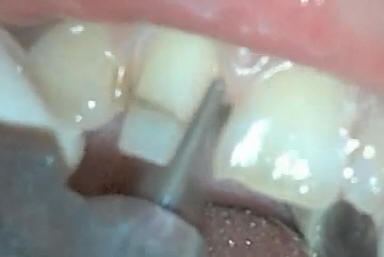

Los hombros en esmalte

son muy marcados |

Con una punta de oxido

de aluminio se redondea el hombro y se pule para una mejor

adaptación de la porcelana |